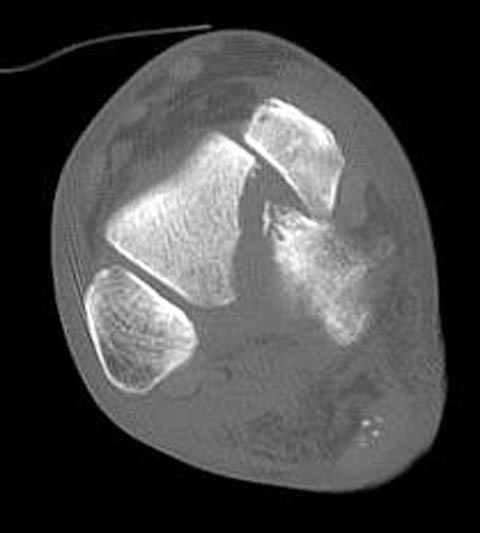

Уважаемые участники русского Ортофорума, поздравляю всех со всеми прошедшими праздниками: Новым годом, Рождеством, Hanukkah, Kwanzaa, желаю участникам всего наилучшего и здоровья.Повреждение таранной кости.Больной 81г автоавария, повреждение таранной кости, здесь снимки. Какие рекомендации?Djoldas Kuldjanov, MDDepartment of Orthopedic SurgerySt. Louis University Medical Center

Вдогонку по поводу перелома таранной кости, больная 81, не страдает диабетом, перелом закрытый, в первый же день поступления ограничились временным наружным фиксатором (как на снимке).

Планировалась открытая фиксация после спадения отека, но больная пожелала лечиться по месту жительству в другом штате..

Примеры на снимке...